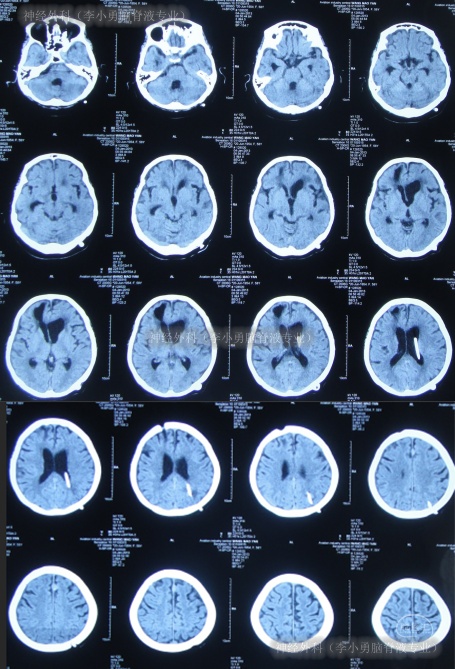

第2家医院出院1月余即2012年2月7日,夜里起夜突然又重复发作以前的症状(恶心呕吐、头昏),且比前2次发作严重,2012年2月8日住入第3家医院:呼和浩特市某三甲医院的神经外科治疗,入院查头颅CT(图-2)和MRI(图-3);脊髓核磁(图-4);肺部CT(图-5)及多次腰椎穿刺脑脊液化验检查(糖低、蛋白高),诊断为:结核性脑膜炎,脑积水。

图-2:2012年2月9日头颅CT

但2012年6月13日(第5家医院治疗22天)凌晨3点患者突发昏迷,体温39.6℃,测血压130/90mmHg,查头颅CT(图-10)后给予甘露醇、退热药物治疗后,体温可逐渐下降,但意识仍不见好转(家属叙述当时抢救了一天一宿)。

图-10:2012年6月13日头颅CT